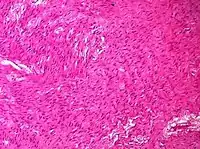

| Sex cord-stromal tumor | Ovarian fibroma | 1.5% | 0% | Spindle-shaped fibroblastic cells and abundant collagen.[8] | ![]() |